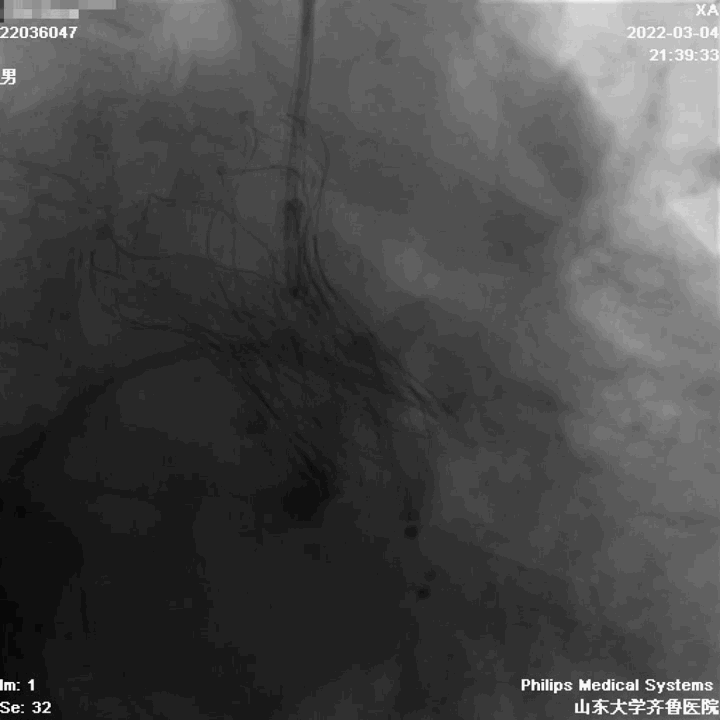

左冠造影

右冠造影

主动脉根部造影

球囊扩张

左冠球囊保护

定位

起始缓慢释放

造影观察

瓣膜工作,造影观察

完全释放

造影

球囊后扩

术中评估球囊扩张效果,放弃已经预装载TAV30瓣膜,植入TAV27型号瓣膜,压差由81mmHg降至5mmHg,EF由38%升至61%。